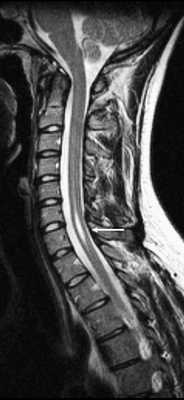

МРТ шейного отдела позвоночника. Локальная киста. Т2-взвешенная сагиттальная МРТ.

Локальная киста обычно наблюдается в месте наибольшего сдавления спинного мозга кистой или грыжей диска. Чаще они наблюдаются при травмах шейного отдела позвоночника. Киста при МРТ позвоночника имеет типичный ликворный сигнал в спинном мозге и может быть окружена зоной миеломаляции.

Сирингомиелитические кисты как отдалённое последствие спинальной травмы встречаются у 3-4% пациентов с неврологическими нарушениями. В целом, они относятся к отдалённым последствиям трамы, хотя известны случаи раннего формирования сирингомиелитических кист. Чаще кисты выявляются при МРТ грудном отделе спинного мозга. Замечена связь сирингомиелитических кист с деформацией позвоночного канала и посттравматическим его стенозом. В отличие от истинной сирингомиелии они развиваются на фоне атрофии и обычно не сопровождаются вздутием спинного мозга. Кисты наблюдаются с одинаковой частотой как выше, так и ниже уровня травмы. Протяжённость кисты может быть любой. Содержимое кисты обычно ликворное, но бывает и с примесью белка, что повышает сигнал от её содержимого на Т1-зависимых МРТ. На Т2-зависимых МРТ в кисте могут быть зоны потери сигнала, что отражает повышенное давление внутри неё. Отмечено, что дренаж кист в этих случаях наиболее эффективен. Изредка при МРТ в кистах встречаются перегородки.

МРТ шейного отдела позвоночника. Кистозно-атрофические изменения. Т2-взвешенная сагиттальная МРТ.